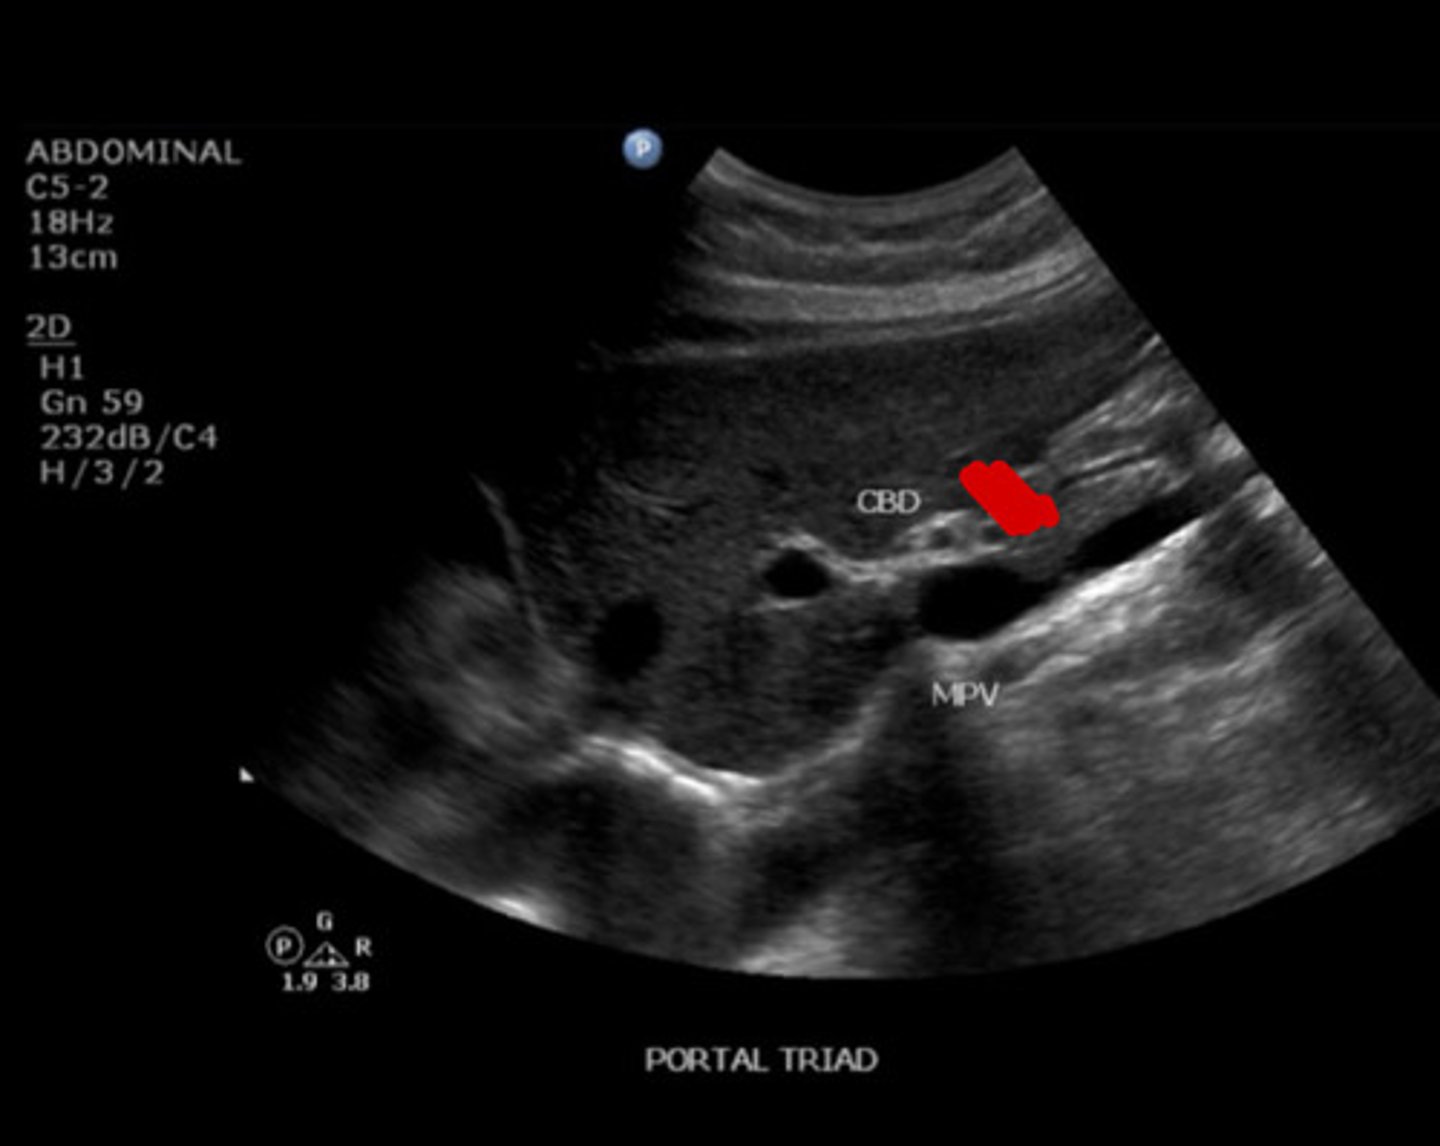

10

New cards

Portal triad

Identify the following;

<p>Identify the following;</p>